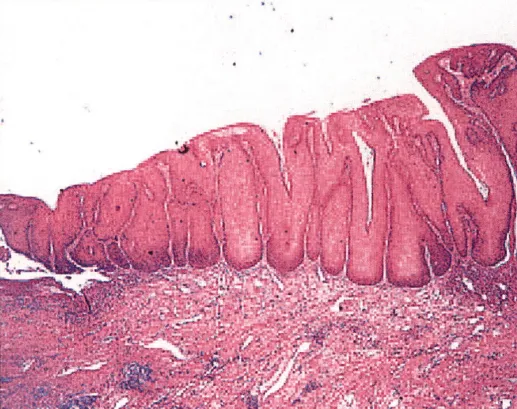

4.疣状癌:高分化,好发于老年女性;细胞分化好,角化层厚,似良性;粗大乳头+缺乏纤维血管轴心及挖空细胞+推挤式浸润(无孤立癌巢)。